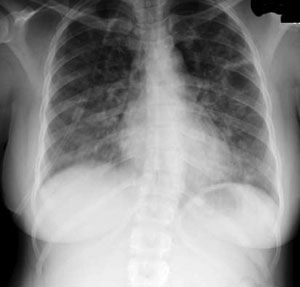

A 54-year-old man presented to the ED with sudden onset of palpitations. His medical history included stage IV renal cell carcinoma, end-stage COPD, NYHA class IV heart failure, recent pulmonary embolism, and ongoing tobacco abuse. Cardiac examination revealed atrial flutter and a rapid ventricular rate.

A CT scan of the thorax was ordered to help determine whether a recurrent pulmonary embolism may have contributed to the arrhythmia.

The patient also had a more than 20-year history of giant bullous emphysema (GBE). He had undergone a left-sided bullectomy in his 40s to help alleviate symptoms. He has continued to smoke and the disease has progressed.

GBE, or “vanishing lung syndrome,” is a rare condition typically found in young men who smoke. It is caused by paraseptal emphysematous bullae that coalesce and eventually compress the lung parenchyma. By definition, the bullae must occupy at least one-third of the hemithorax and thus can be mistaken for a pneumothorax on a standard chest film.